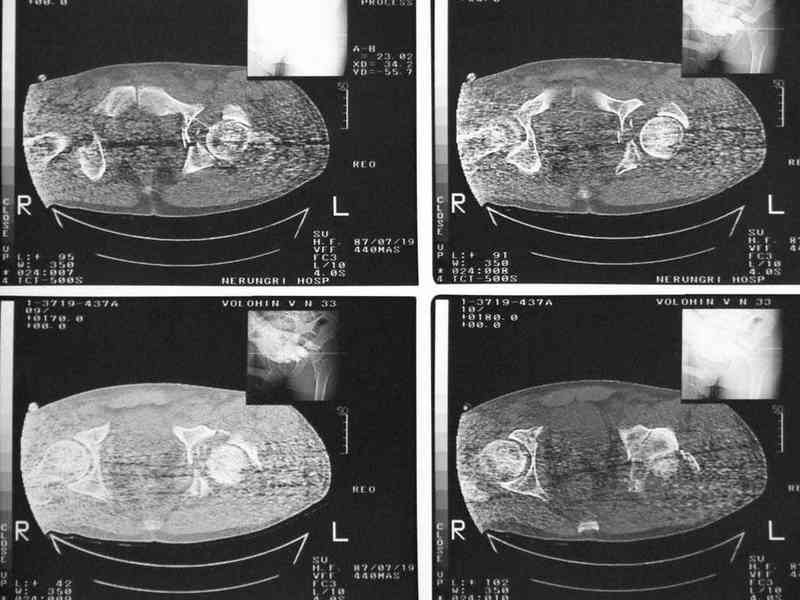

Уважаемые коллеги, нужна помощь, поступил больной с переломом лонной и

седалищной кости слева, перелом вертлужной впадины слева, нестабильный

вывих левой бедренной кости. Попытки вправить бедренную кость -

безуспешны. На данный момент находится на скелетном вытяжении,

посоветуйте какую тактику ведения данного больного выбрать

оптимально.Спасибо.

Имя     : ct3.jpg